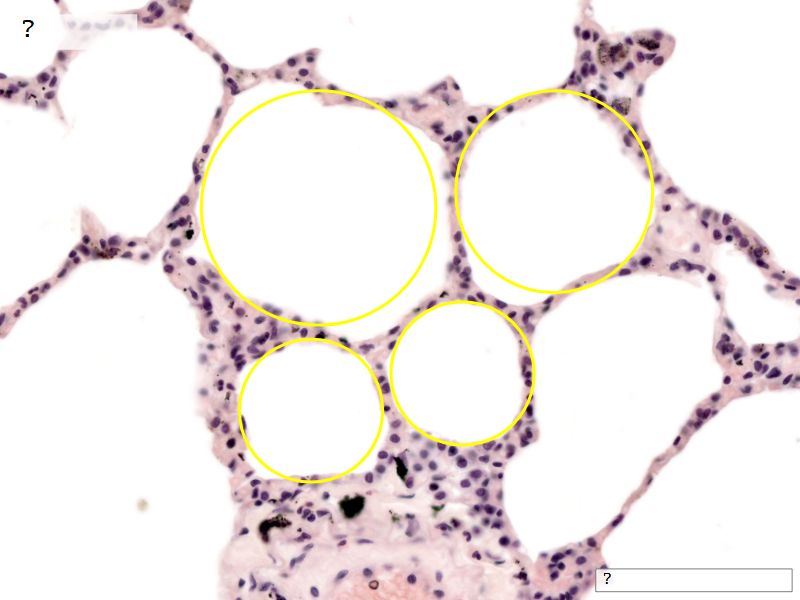

Fill in all the missing labels, and assess as you move through the slides. Answers on the down slide. It is important to do this using pen and paper, and not just glance through the images.